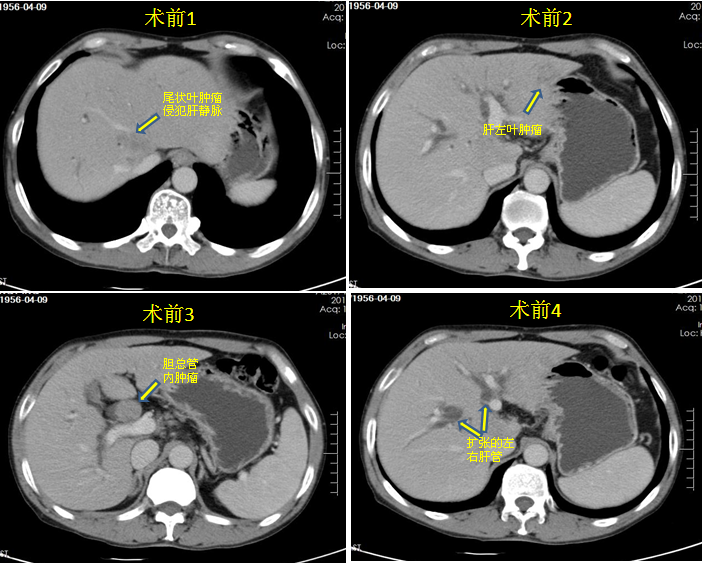

求生的欲望让患者及其家属没有停下求医的步伐,经多方打听,最后在学医的亲戚推荐下,宋先生一家带着一丝希望来到郑州大学五附院,找到了省内著名肝胆外科专家李晓勇教授。李晓勇教授及陈艳军副主任医师反复认真阅读CT片并组织科内医师讨论,发现宋先生的病情有一些特点,肝内多发肿瘤,较大的肿瘤在尾状叶,也是肝脏的中心部位,该处肿瘤已侵犯周围重要的大血管,其余较小的肿瘤局限在肝左外叶,胆管内肿瘤体积较大,但似乎与尾状叶肿瘤连在一起。经过充分讨论,李教授他们认为宋先生的病按照传统的手术方式已无法行根治性切除,但采取多种措施联合治疗还有根治的可能,在详细告知病情及手术方案后,宋先生一家看到了希望,毫不犹豫的接受了李教授的建议。

经过术前积极的准备,手术如期进行。手术由李晓勇教授、陈艳军副主任医师、郜宇主治医师组成的团队共同实施,由胡强夫主任的麻醉团队保障手术安全,杨楠护士长的护理团队通力配合,输血科魏明主任保障手术用血,术中证实肿瘤原发部位在肝尾状叶,肝左叶多个转移灶,胆管内为自尾状叶延续至胆管的癌栓,手术中多种技术手段综合应用,肝脏中心位置的尾状叶肿瘤因侵犯重要血管无法根治性切除,术中在超声引导下避开下腔静脉精准布针,实施目前国际上先进的肿瘤微创技术——纳米刀消融治疗,肝左叶肿瘤实施规则性切除,胆管内癌栓实施根治性切除、胆管空肠吻合,术后在宋伟华护士长的护理团队精心护理下,患者恢复非常顺利,2日后下地行走,3日后进食,术后9天顺利出院。50天后患者来院复查,体重增加了6公斤,各项化验指标都在正常范围,复查CT发现尾状叶肿瘤彻底坏死,完全失去活性。朱先生及其家人感激的说,是李晓勇教授给了患者第二次生命,让他们的家重新充满欢声笑语,感谢纳米刀技术让患者获得新生。